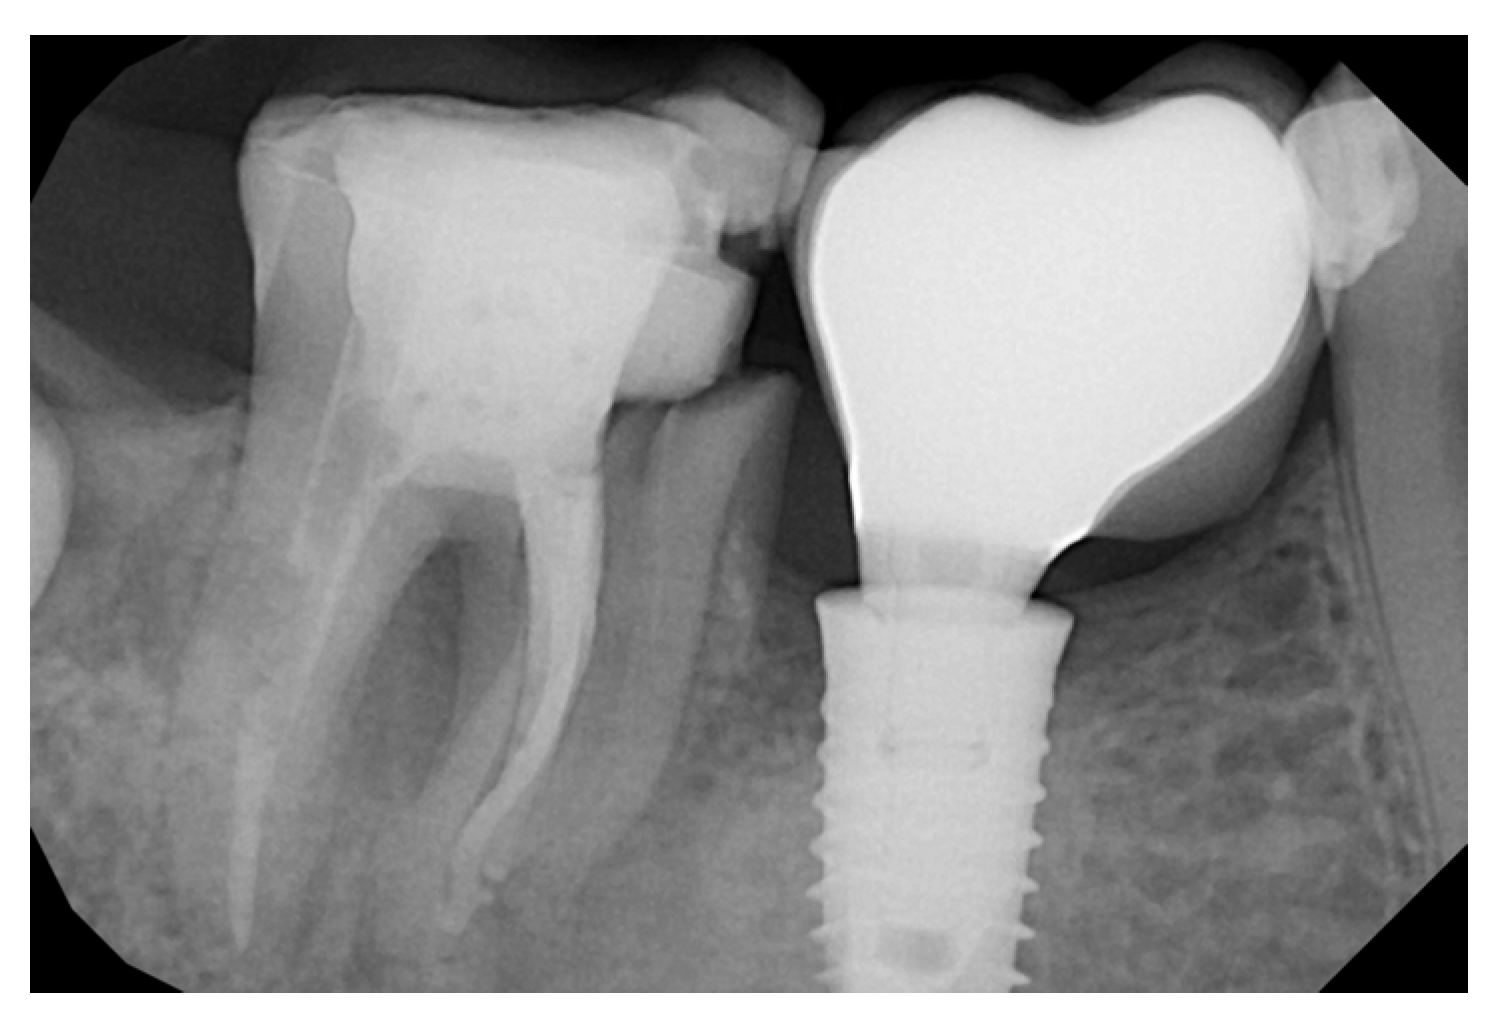

New Operative Protocol for Immediate Post-Extraction Implant in Lower-First-Molar Region with Rex-Blade Implants: A Case Series with 18 Months of Follow-Up

2.2. Surgical Technique